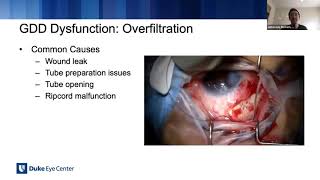

Ahmed glaucoma valve: Managing complications

Ahmed glaucoma valve: Managing complications Lecture: Glaucoma Drainage Devices & Managing Complications

Lecture: Glaucoma Drainage Devices & Managing Complications Lecture: Managing Glaucoma Drainage Device Complications